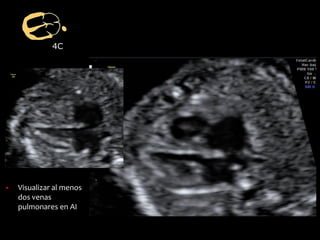

▪ Visualizar al menos

dos venas

pulmonares en AI

4C

▪ Ritmo y frecuencia

▪ Contractilidad